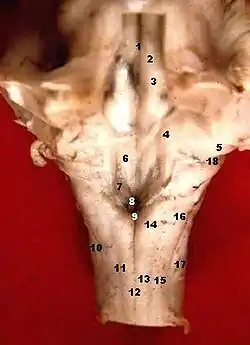

![]() Human caudal brainstem posterior view (Colliculus facialis is #3) | |